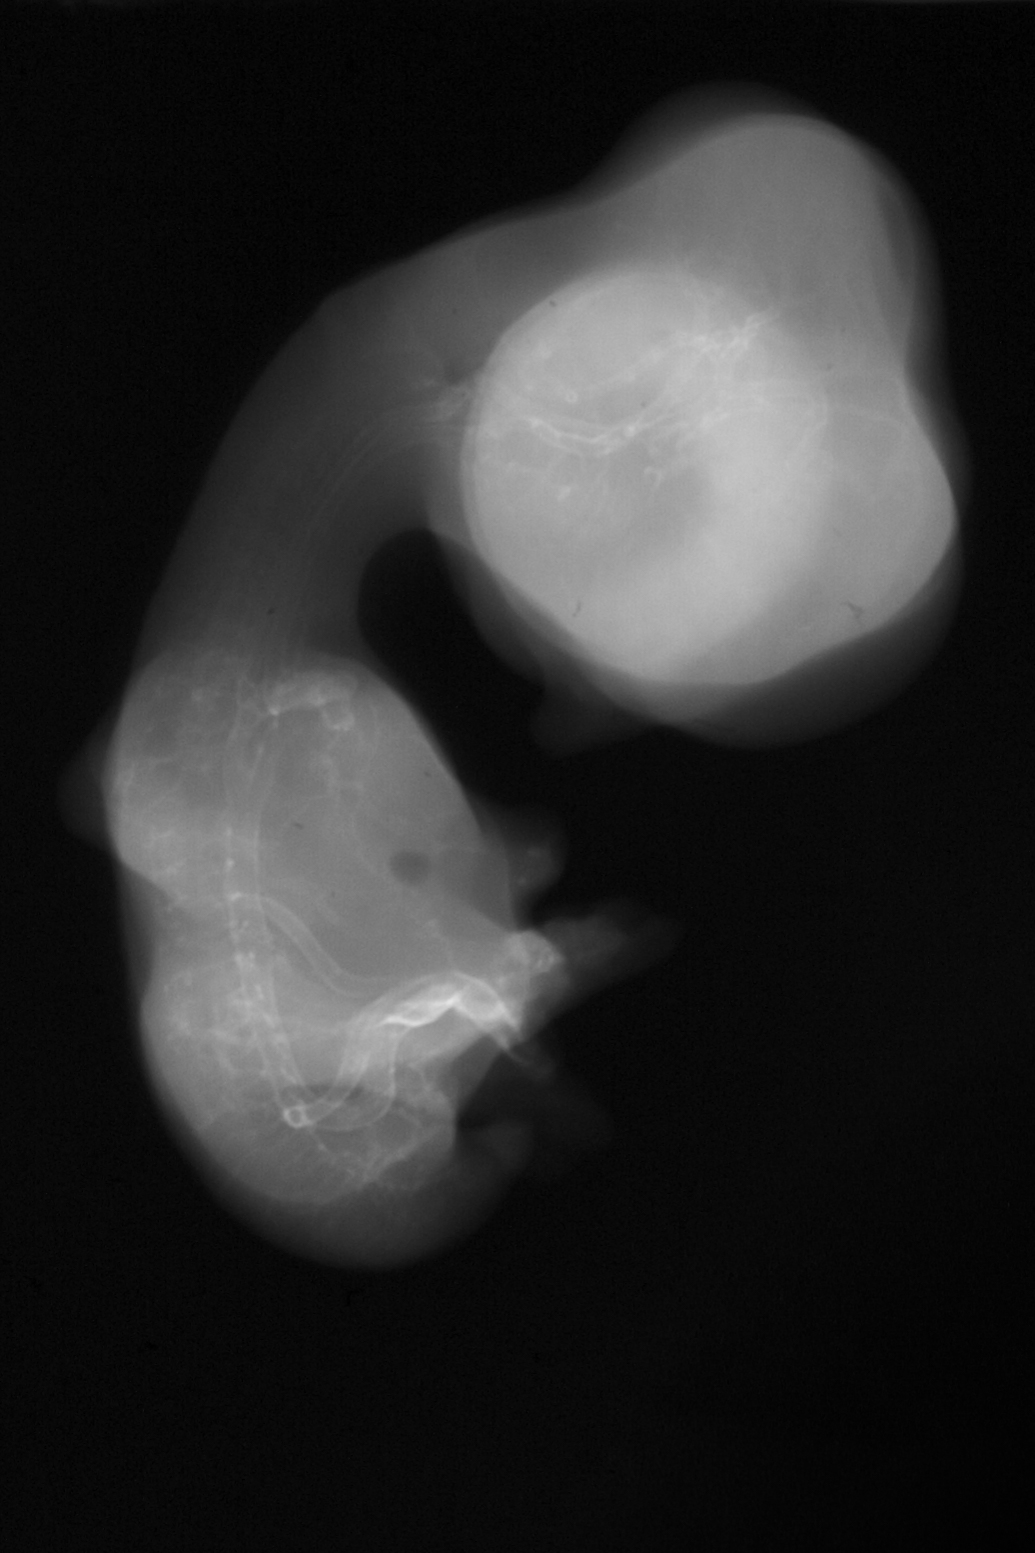

Chick Embryo Microangiography

Hamburger-Hamilton (HH) Stage 31 (approx. 7 days)

X-Ray Micrographs